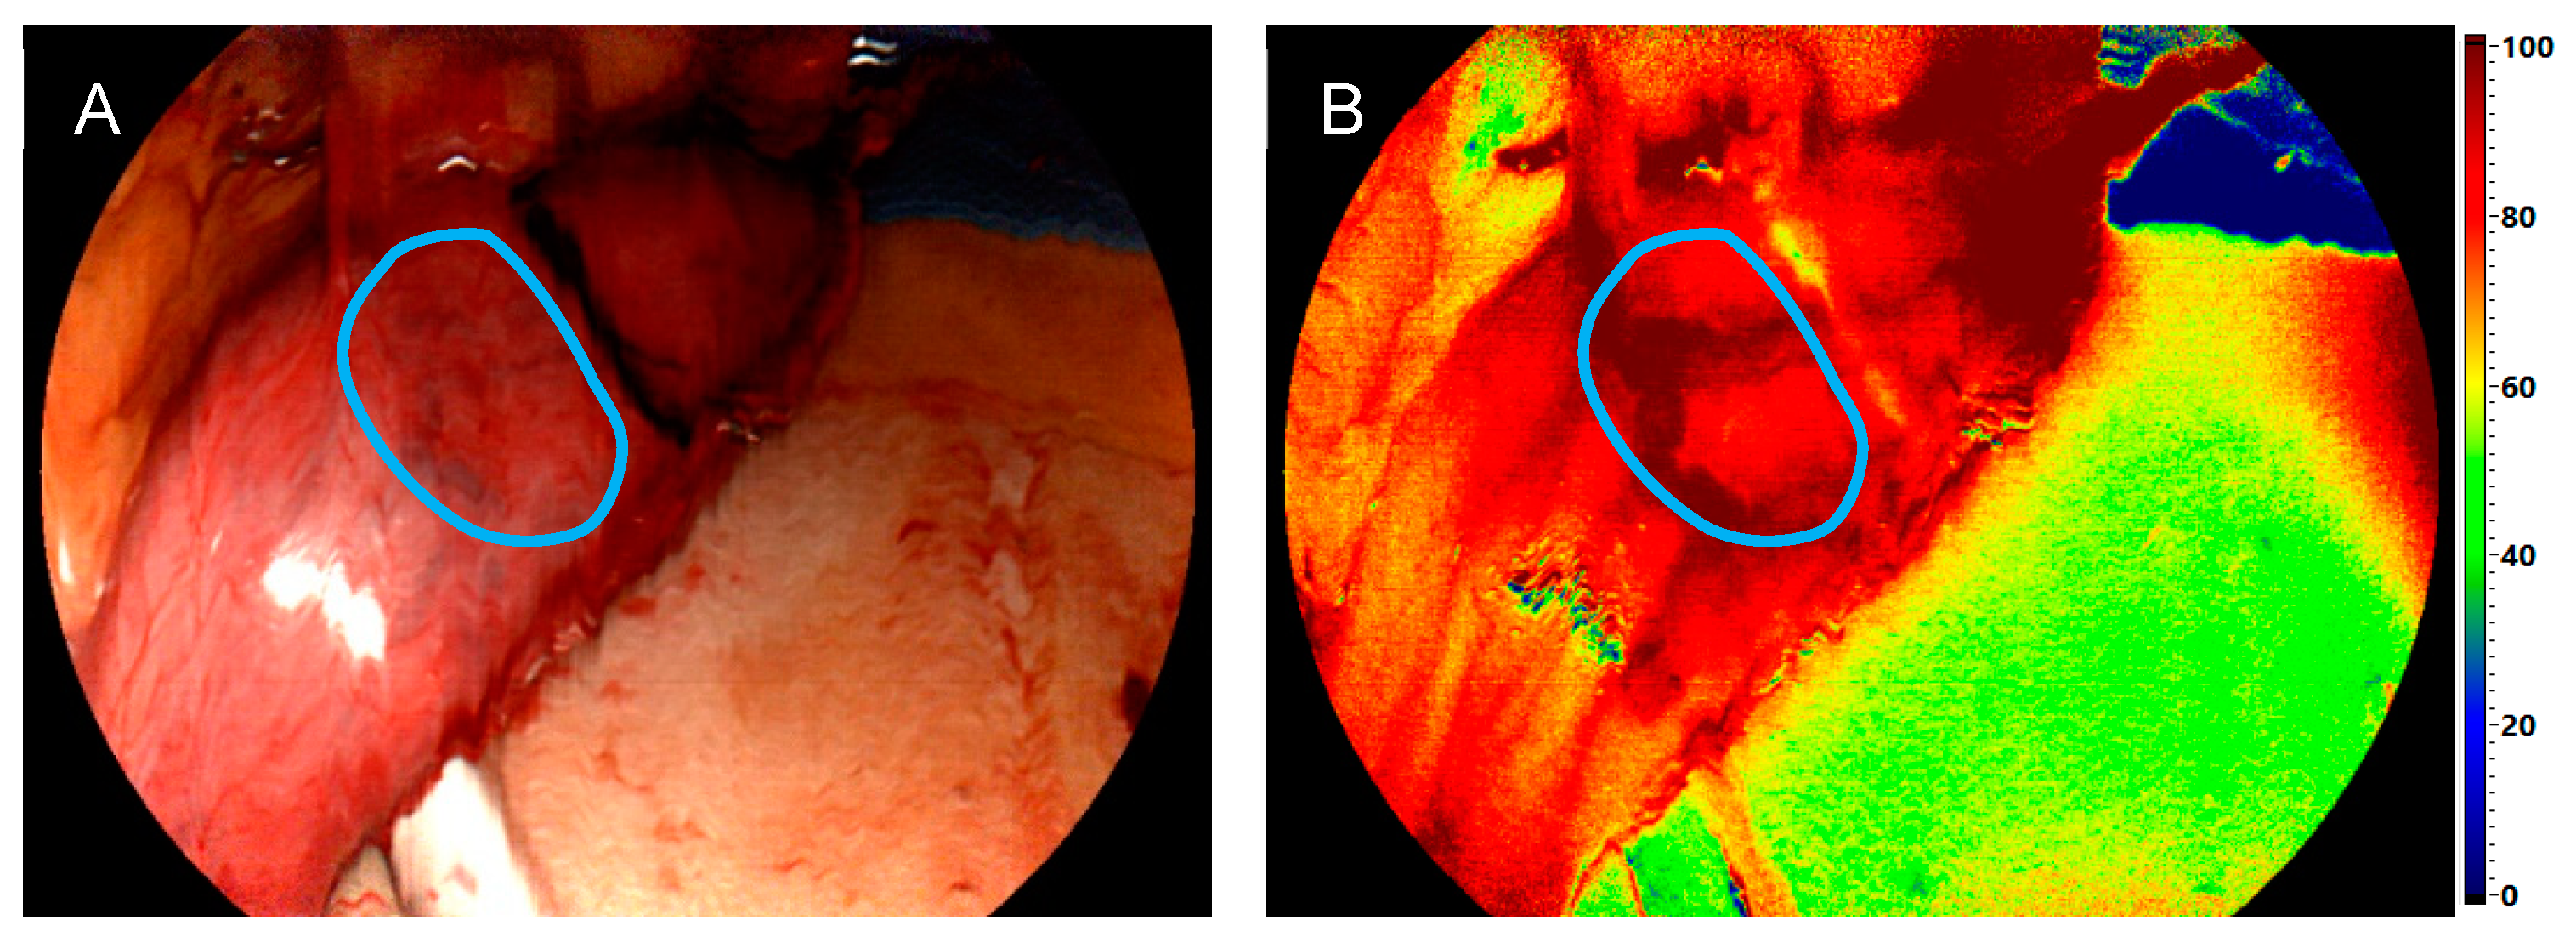

2.2. Surgical Procedure and Hyperspectral Imaging

3.2. Comparison of Intraoperative Perfusion Imaging of the Gastroesophageal Sites (Group 1)

3.3. Perfusion Evaluation of the Gastric Conduit by HSI-MIS (Group 1) and HSI-Open (Group 2)